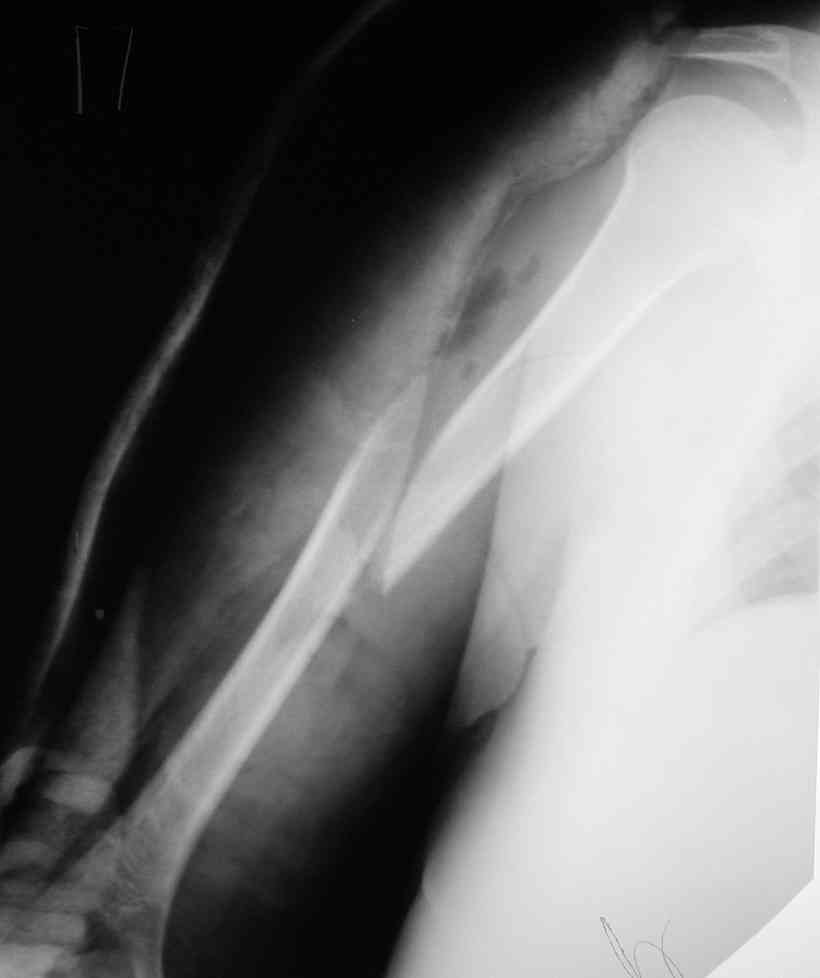

Уважаемые коллеги, с июня 2006 наблюдаем пациентку 46 лет, алкоголичку, с винтообразным переломом плеча.

На 3-й день после травмы переведена с делирием в ПСО другой больницы в гипсовой лонгете. Через неделю возвращена, но уже в отделение гнойной хирургии с вторично открытым инфицированным переломом диафиза плеча и флегмоной. Еще через 3 недели хирурги, переведя острый гнойный процесс в хронический вялотекущий, позвали травматолога с целью "сделайте что-нибудь с переломом". Сделали: резекцию остеомиелитичекого очага (перелома, плавающего в гною) около 7 см; стержневой аппарат; цементный спейсор в дефект кости (укоротили плечо на 3 см. и 4 см осталась дырка), бусы из того же цемента с антибиотиком в мягкие ткани. Снимки приложены.

27.11 в состоянии не прекращающегося после выписки опьянения получила закрытый надмыщелковый перелом плеча на уровне дистальных блокирующих винтов в результате адекватной травмы. Снимки прилагаются.